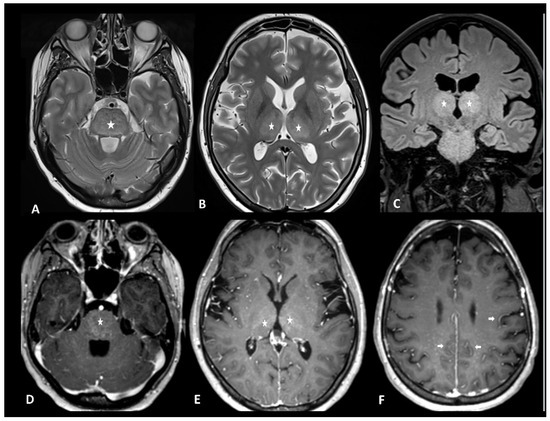

2.1.1. Ir-Encephalitis

| CNS | Encephalitis | CE brain MRI + LP + EEG + autoantibodies | Infectious encephalitis, disease progression | Mesiotemporal T2/FLAIR hyperintensities |

3.1. Immune Effector Cell-Associated Neurotoxicity Syndrome

| CNS | ICAN | LP + CE brain MRI + EEG | Toxic leukoencephalopathy | Bilateral thalami and brainstem T2/FLAIR hyperintensity |